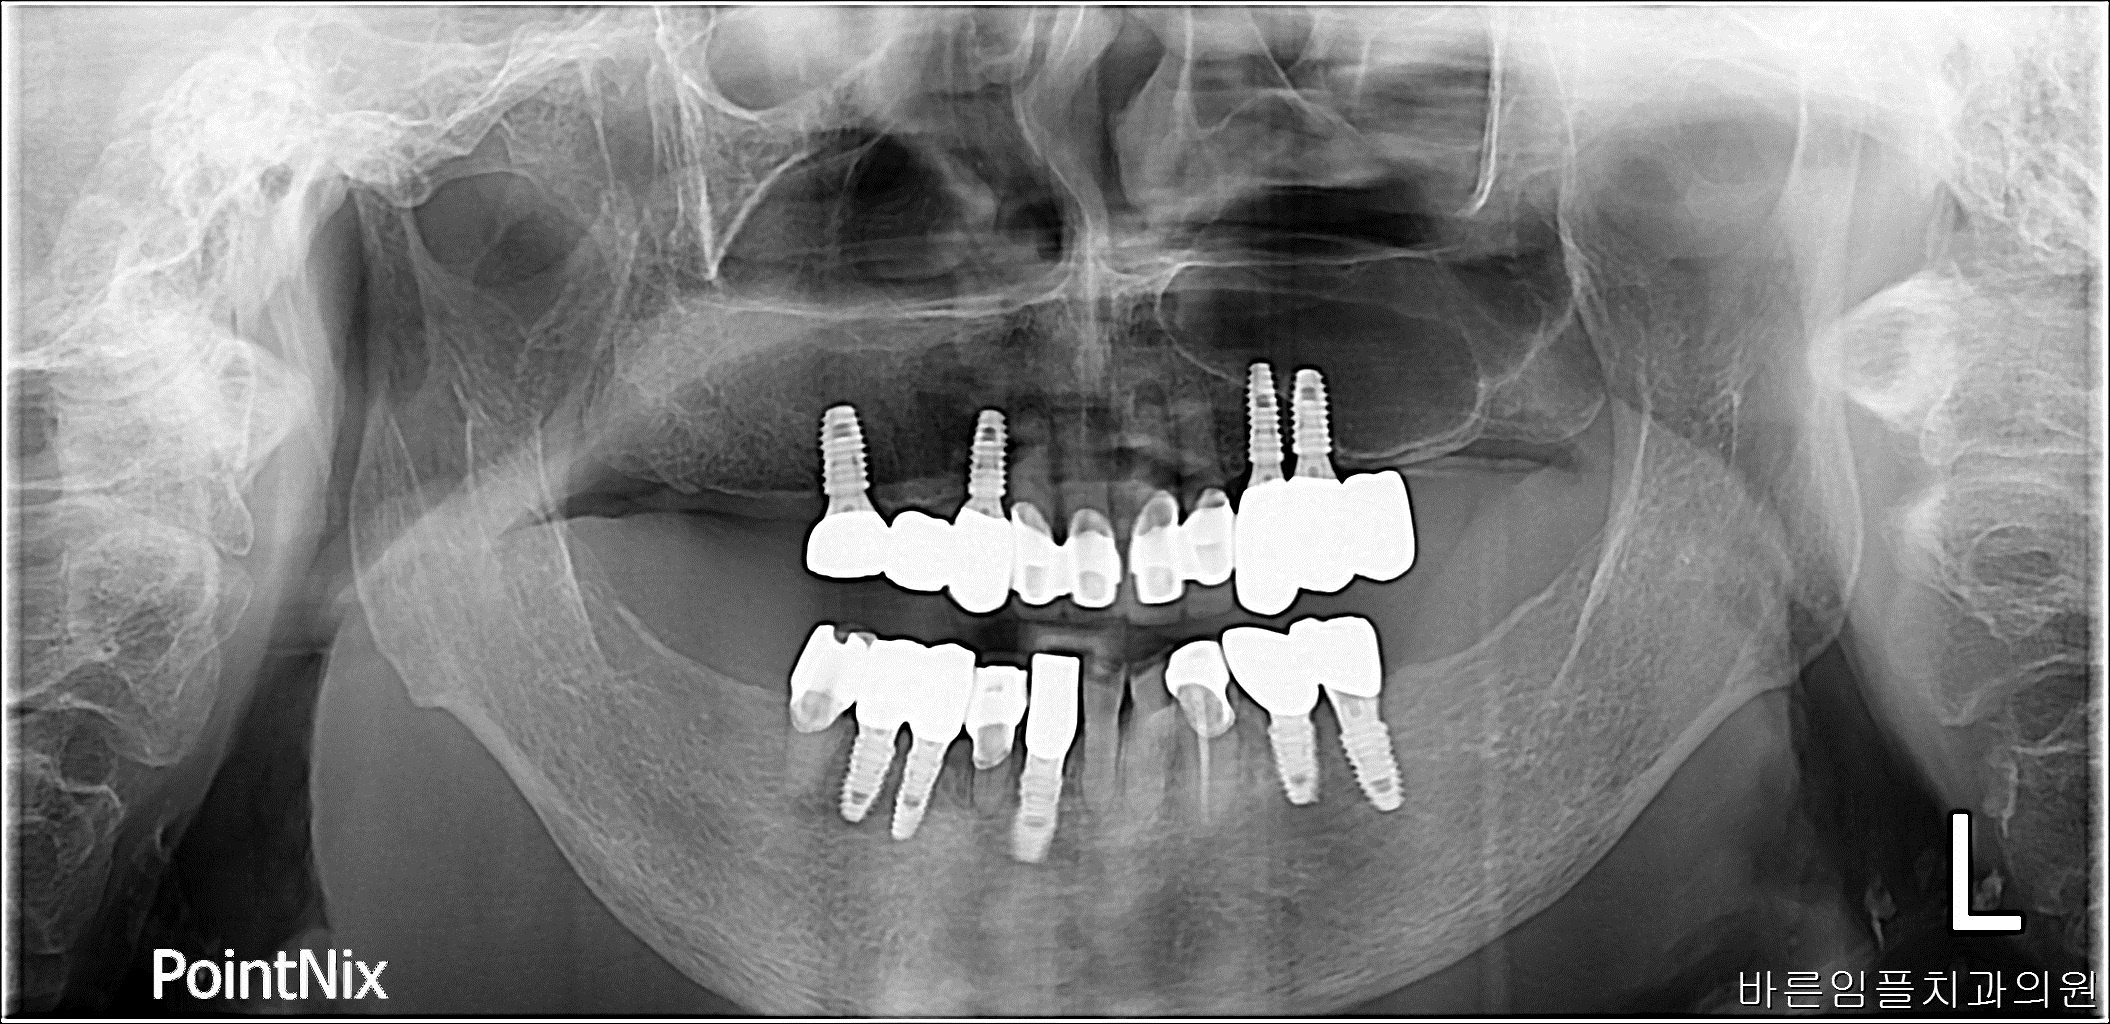

이ㅇㅇ / 수면임플란트 페이지 정보 작성일 23-10-27 17:03 2023-03-02 이ㅇㅇ Before 2023-08-05 이ㅇㅇ After 이ㅇㅇ / 수면임플란트 목록 이전글차ㅇㅇ / 수면임플란트 다음글 박ㅇㅇ / 수면임플란트